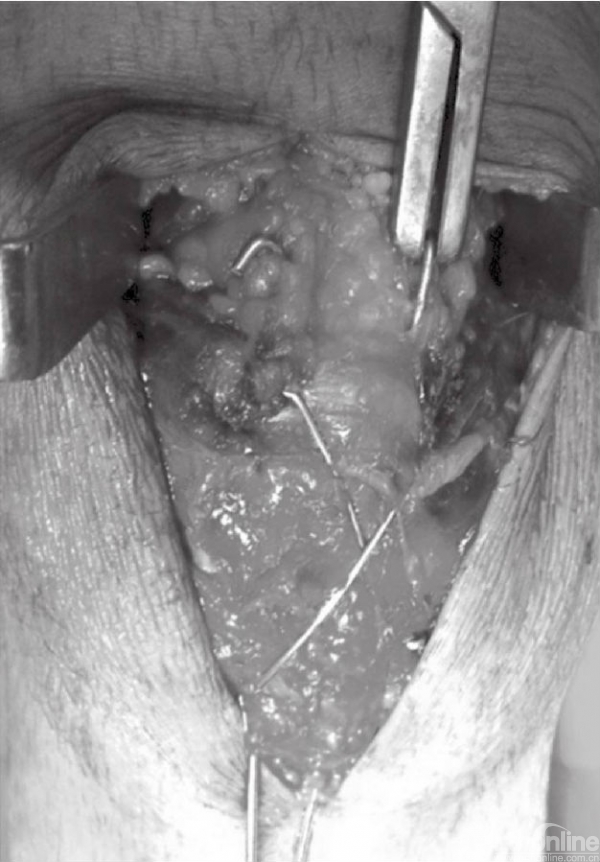

在张力带旋紧固定后,用钢丝剪剪除多余钢丝。突出的部分折弯后贴近髌骨上极放置(图15)。克氏针末端用折弯器折弯后尽量贴近髌骨表面。钢丝末端旋转后经股肌间隙埋入股四头肌腱(图16)。后期缝合肌间隙,可防止克氏针退出。克氏针远端在近髌骨处切断(图17)。用不可吸收线缝合撕裂的支持带(图18)。屈膝90°,以评估内固定的稳定性(图19)。

图18 在髌骨两侧用不可吸收缝线缝合撕裂的支持带

图19 屈膝90°,评估内固定的稳定性